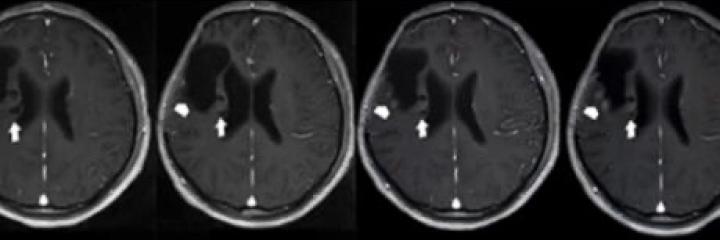

Brain Cancer

A drug molecule co-identified by our research team offers hope of longer life to chemo-resistant patients of a rare and deadly type of brain cancer – secondary glioblastoma.